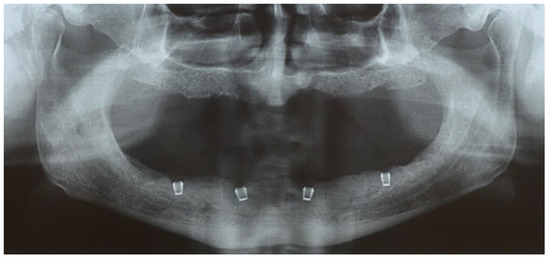

Edentulous Mandibles Restored with Fiber-Reinforced Composite Prostheses Supported by 5.0 mm Ultra-Short Implants: Ten-Year Follow-Up

2. Materials and Methods

3. Results